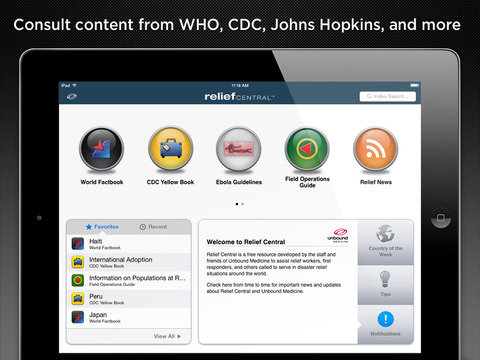

Relief Central is a free mobile and web resource developed by staff and friends of Unbound Medicine. It includes the latest versions of The World Factbook from the CIA, CDC Health Information for International Travel (The Yellow Book), the Field Operations Guide from USAID, Prime PubMed Search, and Relief News from the Red Cross, United Nations, US Centers for Disease Control, CDC, FEMA, and more.

THE WORLD FACTBOOK

The World Factbook from the US Central Intelligence Agency (CIA) contains detailed information on the history, people, government, economy, geography, communications, transportation, military, and transnational issues for 266 world countries and territories.

CDC YELLOW BOOK (Health Information for International Travel)

USAID FIELD OPERATIONS GUIDE

The Field Operations Guide from USAID delivers disaster assessment and response information and includes chapters and appendices ranging from information on populations at risk to commonly used acronyms, all arranged in an outline format.

RELIEF NEWS

Relief News puts the latest news at your fingertips with a collection of RSS feeds from trusted non-profit groups, international organizations, and government agencies. Feeds are from the Red Cross, United Nations, US Centers for Disease Control and Prevention (CDC), US Federal Emergency Management Agency (FEMA), ReliefWeb, and more.